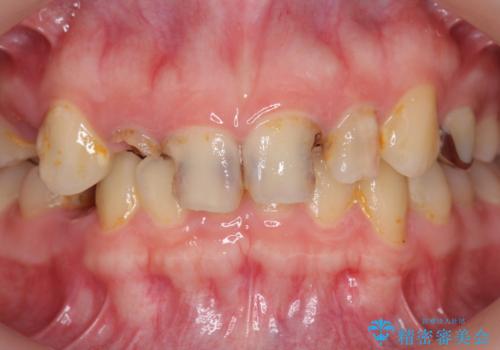

- 放置した虫歯の歯がボロボロになってしまい治療を希望され来院されました。

残根状態の歯、神経まで虫歯が達し失活した歯、歯肉縁下まで及んだ虫歯が多数認められます。

まず虫歯を拡大鏡、マイクロスコープ下で丁寧に取り除き歯肉縁下の虫歯を歯周外科により解決したのち、ジルコニアクラウン製作を行っていきます。